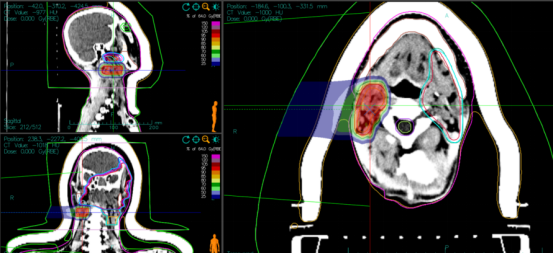

1. **Target Delineation:**

- GTV: MRI-indicated irregular nodules and masses in the left nasal cavity, nasopharynx, oropharynx, left maxillofacial region, periorbital area, and nasal root, including surrounding invaded tissues. A 0.5 cm margin was added to form PTVboost.

- CTV: High-risk areas based on GTV, with appropriate cropping in the right eye and right optic nerve. A 0.3 cm margin was added to form PTV1.

- GTVnd_R: Enlarged lymph nodes in the right neck level II.

- GTVnd_L: Enlarged lymph nodes in the left neck levels Ib and II.

- CTVnd_R: Lymph node drainage area in the right neck level II.

- CTVnd_L: Lymph node drainage area in the left neck levels Ib-II.

A 0.3 cm margin was added to form PTVnd_R and PTVnd_L.

2. **Prescription Dose:**

- PTVboost: 8 Gy(RBE)/2 fractions

- PTV1, PTVnd_R, PTVnd_L: 64 Gy(RBE)/16 fractions

- Total dose to the tumor area: 72 Gy(RBE)/18 fractions

Figure 1: The total dose to the tumor region reached 72 Gy (RBE).

Figure 2: PTVnd_L 64 Gy (RBE)/16 fx.

Figure 3: PTVnd_R 64 Gy (RBE)/16 fx, with the total dose to the tumor region reaching 72 Gy (RBE).